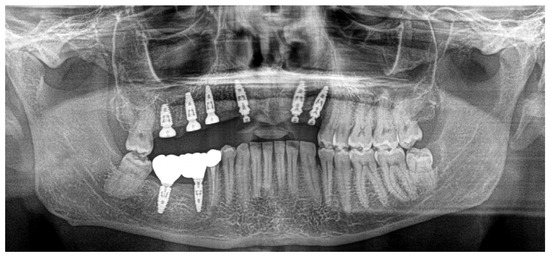

In November 2023, teeth 16 and 17 were also extracted, always with the same surgical protocol of decontamination and photobiomodulation (Figure 8).

In June 2024, the implants were inserted in areas 16 and 17. Three months after the insertion of the last implants in 16-17 (4.2 × 10 mm and 4.2 × 8 mm, Biotech Dental, Allée de Craponne, Salon de Provence, France), it was possible to proceed with the digital impression-taking to proceed with a temporary prosthesis in PMMA (Figure 9) after a radiographic control (Figure 10).

The case has now been finalized, and the radiographic follow-up shows a stability of the bone regenerations obtained (Figure 11), with no new external root resorptions on the residual teeth.

Figure 8. Teeth 16 and 17 extracted with an external cervical resorption (ECR).

Figure 10. OPT after all implant placements, in July 2024.

Figure 11. Radiographic follow-up in November 2024.